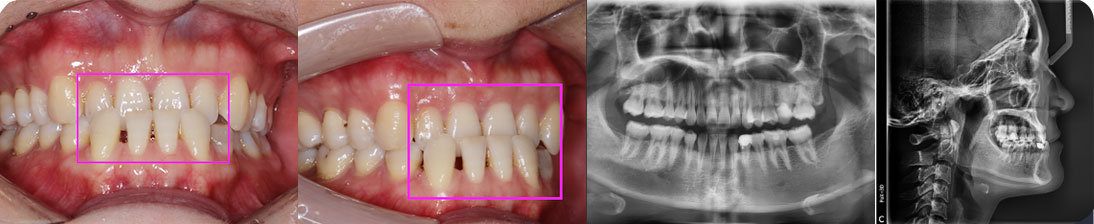

- 【診斷】

骨性Ⅱ類高角伴擁擠

上頜前突、下頜后縮、下前牙唇傾

下中線右偏2.5mm,21 35°扭轉(zhuǎn)13低位

打造醫(yī)生:德倫口腔正畸中心熊小琴主任

- 【治療方案】

拔除3顆多余的咬合不正的智齒,通過(guò)支抗釘控制

失狀向和垂直向,推上、下牙遠(yuǎn)移解決擁擠改善前

突,使整個(gè)頜平面逆時(shí)針旋轉(zhuǎn),改善了下頜后縮的

情況

矯治前后對(duì)比

牙列整平排齊,前牙內(nèi)收;覆蓋、覆合正常;尖牙和磨牙達(dá)到中性關(guān)系;上下中線對(duì)齊;下頜后縮改善